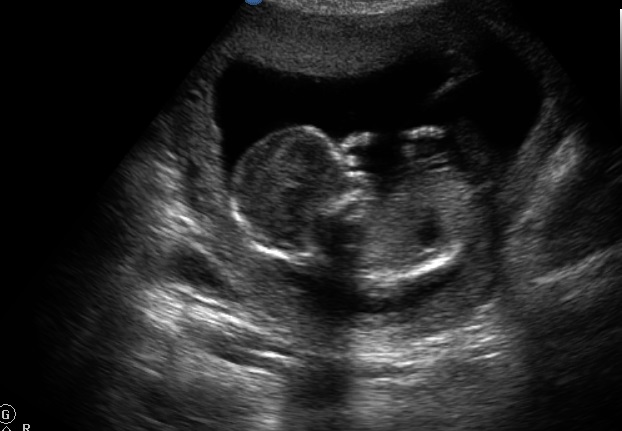

I am new and have read lots but cannot seem to figure out what I am looking for to predict a boy or girl on ultrasound. Any guesses? I have no idea if there is a nub here or not. Any guesses appreciated!